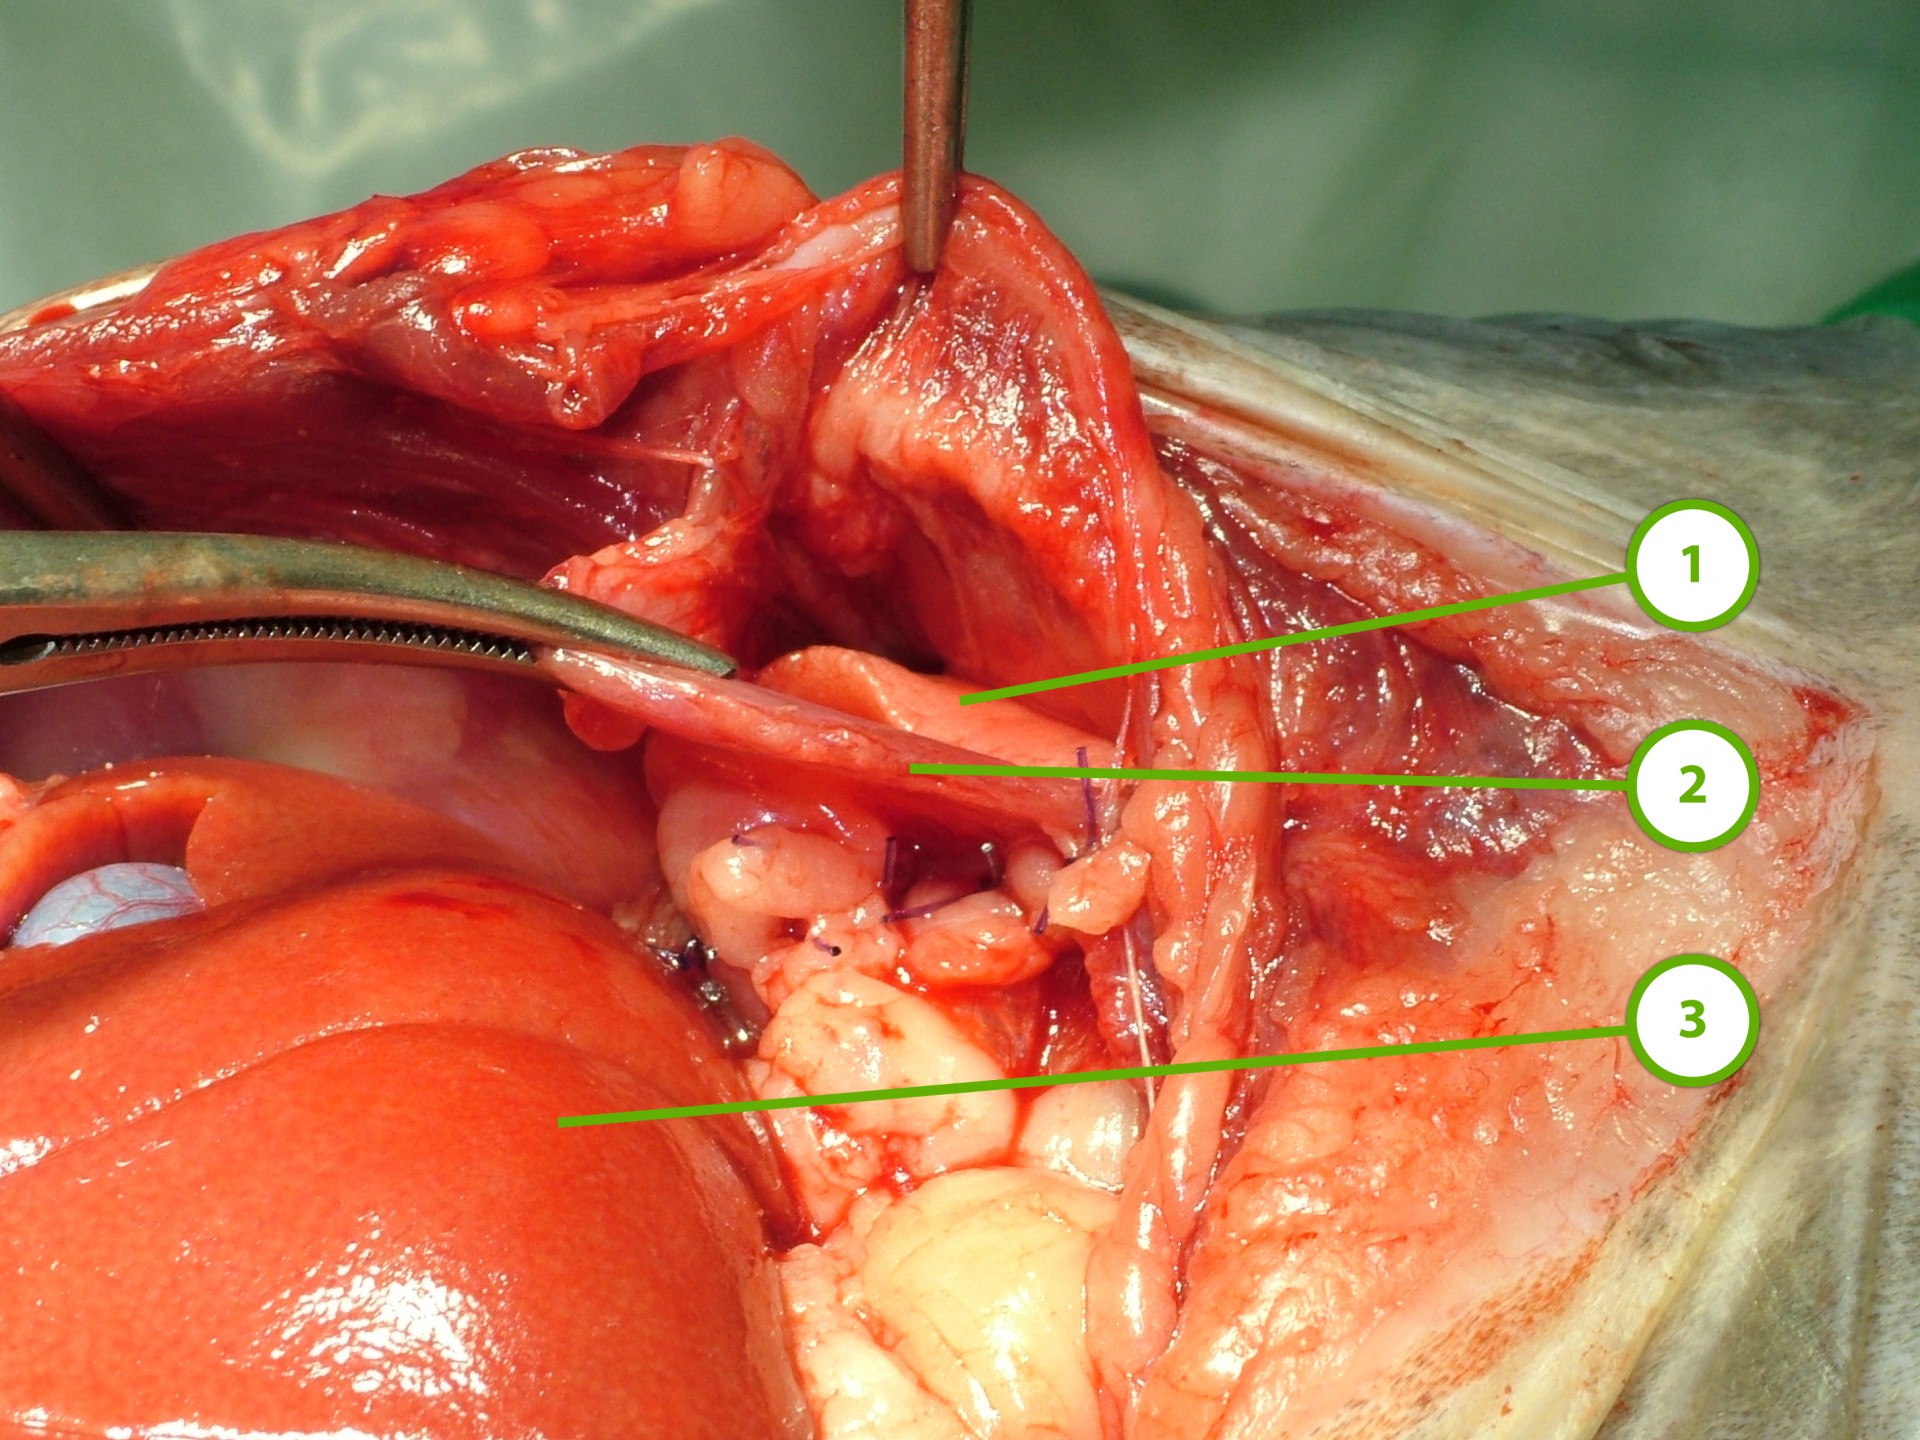

Mindhárom rekeszsérv forma meglehetősen ritkán fordul elő. A diagnózis felállítása a kórelőzmény, a klinikai tünetek a mellkas röntgenvizsgálata, a hasüreg ultrahangos vizsgálata alapján lehetséges.A rekeszsérv műtéti ellátása során a legnagyobb kihívást az jelenti, hogy a hasüreg megnyitását követően a sérvkapun keresztül levegő kerül a mellüregbe, ezáltal az állat spontán légzése leáll, így a műtét teljes ideje alatt asszisztált lélegeztetésre van szüksége.A műtét során a mellkasba előesett szerveket reponáljuk, a rekesz folytonosság hiányát megszüntetjük és a mellkasban lévő szabad levegőt eltávolítjuk, ezzel biztosítva az állat spontán légzését. A műtétet követő napokban legfontosabb feladat a vérkeringés és a légzés folyamatos, kórházi körülmények közötti kontrolálása.Az idejében felismert és megfelelően ellátott veleszületett rekeszsérv jó eséllyel gyógyítható, a traumás eredetű sérv ellátásának eredményességét általában az egyéb szervek sérülése határozza meg.